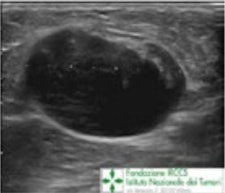

A 65-year-old patient presented with a recent history of a new lump in the left axilla. Clinical examination confirmed a discrete hard palpable mass in the left axilla, in keeping with suspicious finding without clinical breast abnormalities. Mammography and ultrasound were required. Corresponding to the palpable lump, on left mammogram (top) is a rounded mass without any breast lesions, and on ultrasound (bottom) a hypoechoic lesion with no hilum, in keeping with malignant metastatic lymph node. All images courtesy of Dr. Pietro Panizza.

Same patient as above. A second-look ultrasound was performed demonstrating an ill-defined, irregular lesion corresponding to the enhancing lesion on MRI. It was biopsied. At histology, it was an invasive ductal carcinoma, and the patient underwent conservative surgery. Chemotherapy was discussed and agreed upon in the multidisciplinary meeting."As radiologists, working in a multidisciplinary team leads to a better comprehension of the whole treatment strategy; we can for example, compare imaging with pathological results and discordant cases can be easily identified and opportunely/conveniently followed-up," they said. "We can be more involved in the care pathway not only as a diagnostic service, but also in the follow-up of neoadjuvant therapy, establishing together with clinicians the best imaging technique for every patient."